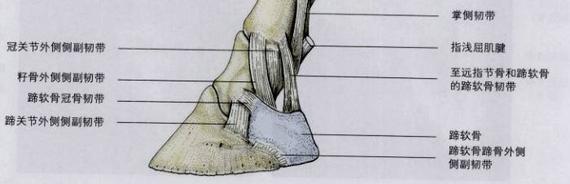

小小的蹄子里面有骨骼、关节、肌腱、腱鞘、韧带、软骨等结构,这些结构对蹄的功能都是非常重要的,任何一个损伤都会产生跛行,甚至有可能出现严重的后果。